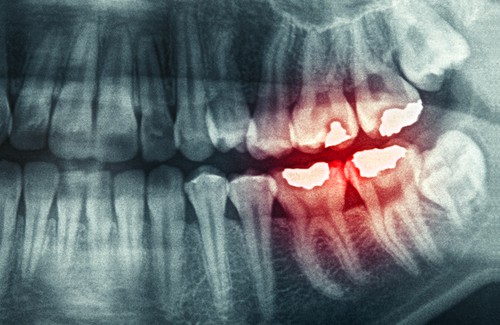

- For tidlig tannerosjon.

- Fraktur i tennene.

- Tap av tannemaljen.